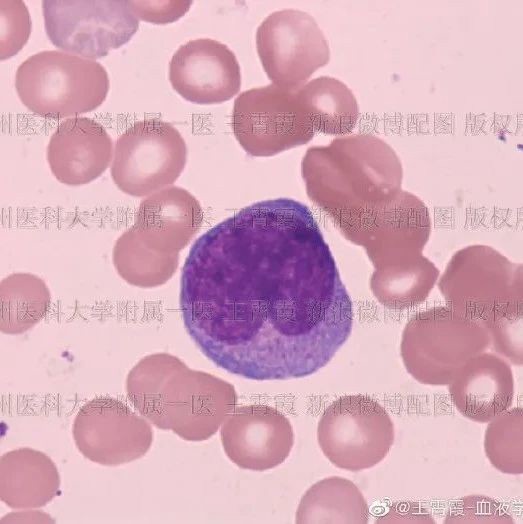

按ITP治疗七年未果,形态学助力罕见病诊断

2025-07-04 -

耳聋背后隐藏的真相——以突聋为首发症状的慢性粒细胞白血病一例

看图识细胞,提升形态学基本功 | 形态学周考